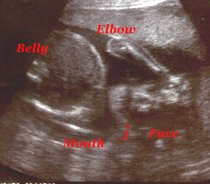

This is my hand up by my face.

Still up by my face.

I got a good profile.